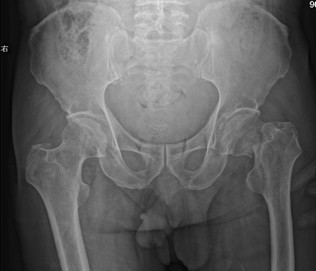

一般情况介绍 患者张XX,男,69岁,因“跌倒致左髋疼痛、活动障碍6天”入院。既往史:“糖尿病”15年,一直服“拜糖平”、“二甲双胍”治疗,血糖控制在 7~15mmol/L之间。高血压病史4年,最高达180/90mmHg,未系统服药治疗。曾有脑梗塞病史,2月前因“双侧颈动脉粥样硬化、右颈内动脉中 度狭窄”行右颈动脉支架成形术,现服用波立维、拜阿斯匹林联合抗血小板治疗。查体:左髋部无肿胀、瘀斑,关节活动受限,叩痛、压痛(+),左下肢外旋 60°畸形。双足多处皮肤破溃坏死,创面干燥,右足足背动脉搏动不明显。影像学资料:骨盆正位、左侧髋关节侧位示“1、左侧股骨颈骨折;2、骨盆骨质疏 松”(图1、2)。颈动脉超声示“双侧颈动脉粥样硬化伴多发斑块”(图3)。下肢动脉彩超示“双下肢动脉粥样硬化闭塞症声像;右侧胫前及左侧胫前、足背、 胫后动脉广泛狭窄(中-重度);右足背动脉狭窄(轻度)” (图4)。下肢静脉彩超示“左下肢深静脉血栓栓塞声像:左侧腓静脉(后一条)及左小腿多发肌间静脉完全栓塞。双侧股静脉及腘静脉血流缓慢。余双下肢深静脉 及大隐静脉近段未见明显异常声像” (图5)。心脏彩超示“主动脉硬化、主动脉瓣退行性变;左房增大,心内血流未见明显异常;左室收缩功能未见异常,舒张功能减退”。血生化指标:凝血四项示 “纤维蛋白原6.64g/L”,D-二聚体“1499ng/ml”。结合患者病史、体征及辅助检查,诊断“1、左股骨颈骨折;2、Ⅱ型糖尿病;3、高血压 病;4、脑梗塞后遗症;5、右颈动脉支架成形术后”。请内分泌科、心血管内科会诊,停用波立维、拜阿斯匹林,行降糖、降压、营养支持等对症治疗。入院后两 周在气管插管全麻下行“左侧人工股骨头置换术”,术程顺利。患者麻醉清醒后即嘱其行双下肢肌肉主动舒缩及膝踝关节屈伸活动,术后12h开始首次应用磺达肝 癸钠2.5mg皮下注射,以后每天以同等剂量皮下注射一次。患者术后5天即可在助行器帮助下下床活动,磺达肝癸钠持续用至10天停止,并防治感染、降糖、 降压、营养支持治疗。治疗期间每日观察患肢是否有肿胀情况,测量双侧大腿及小腿周径并记录。术后两周复查双下肢动静脉彩超,与术前结果相同;行肺部X线片 及CT检查,未见肺动脉栓塞征象。骨盆X线片示人工股骨头置换术后改变,人工假体位置佳(图6)。患者顺利出院,并恢复波立维、拜阿斯匹林联合抗血小板治 疗。

图1 术前骨盆正位片